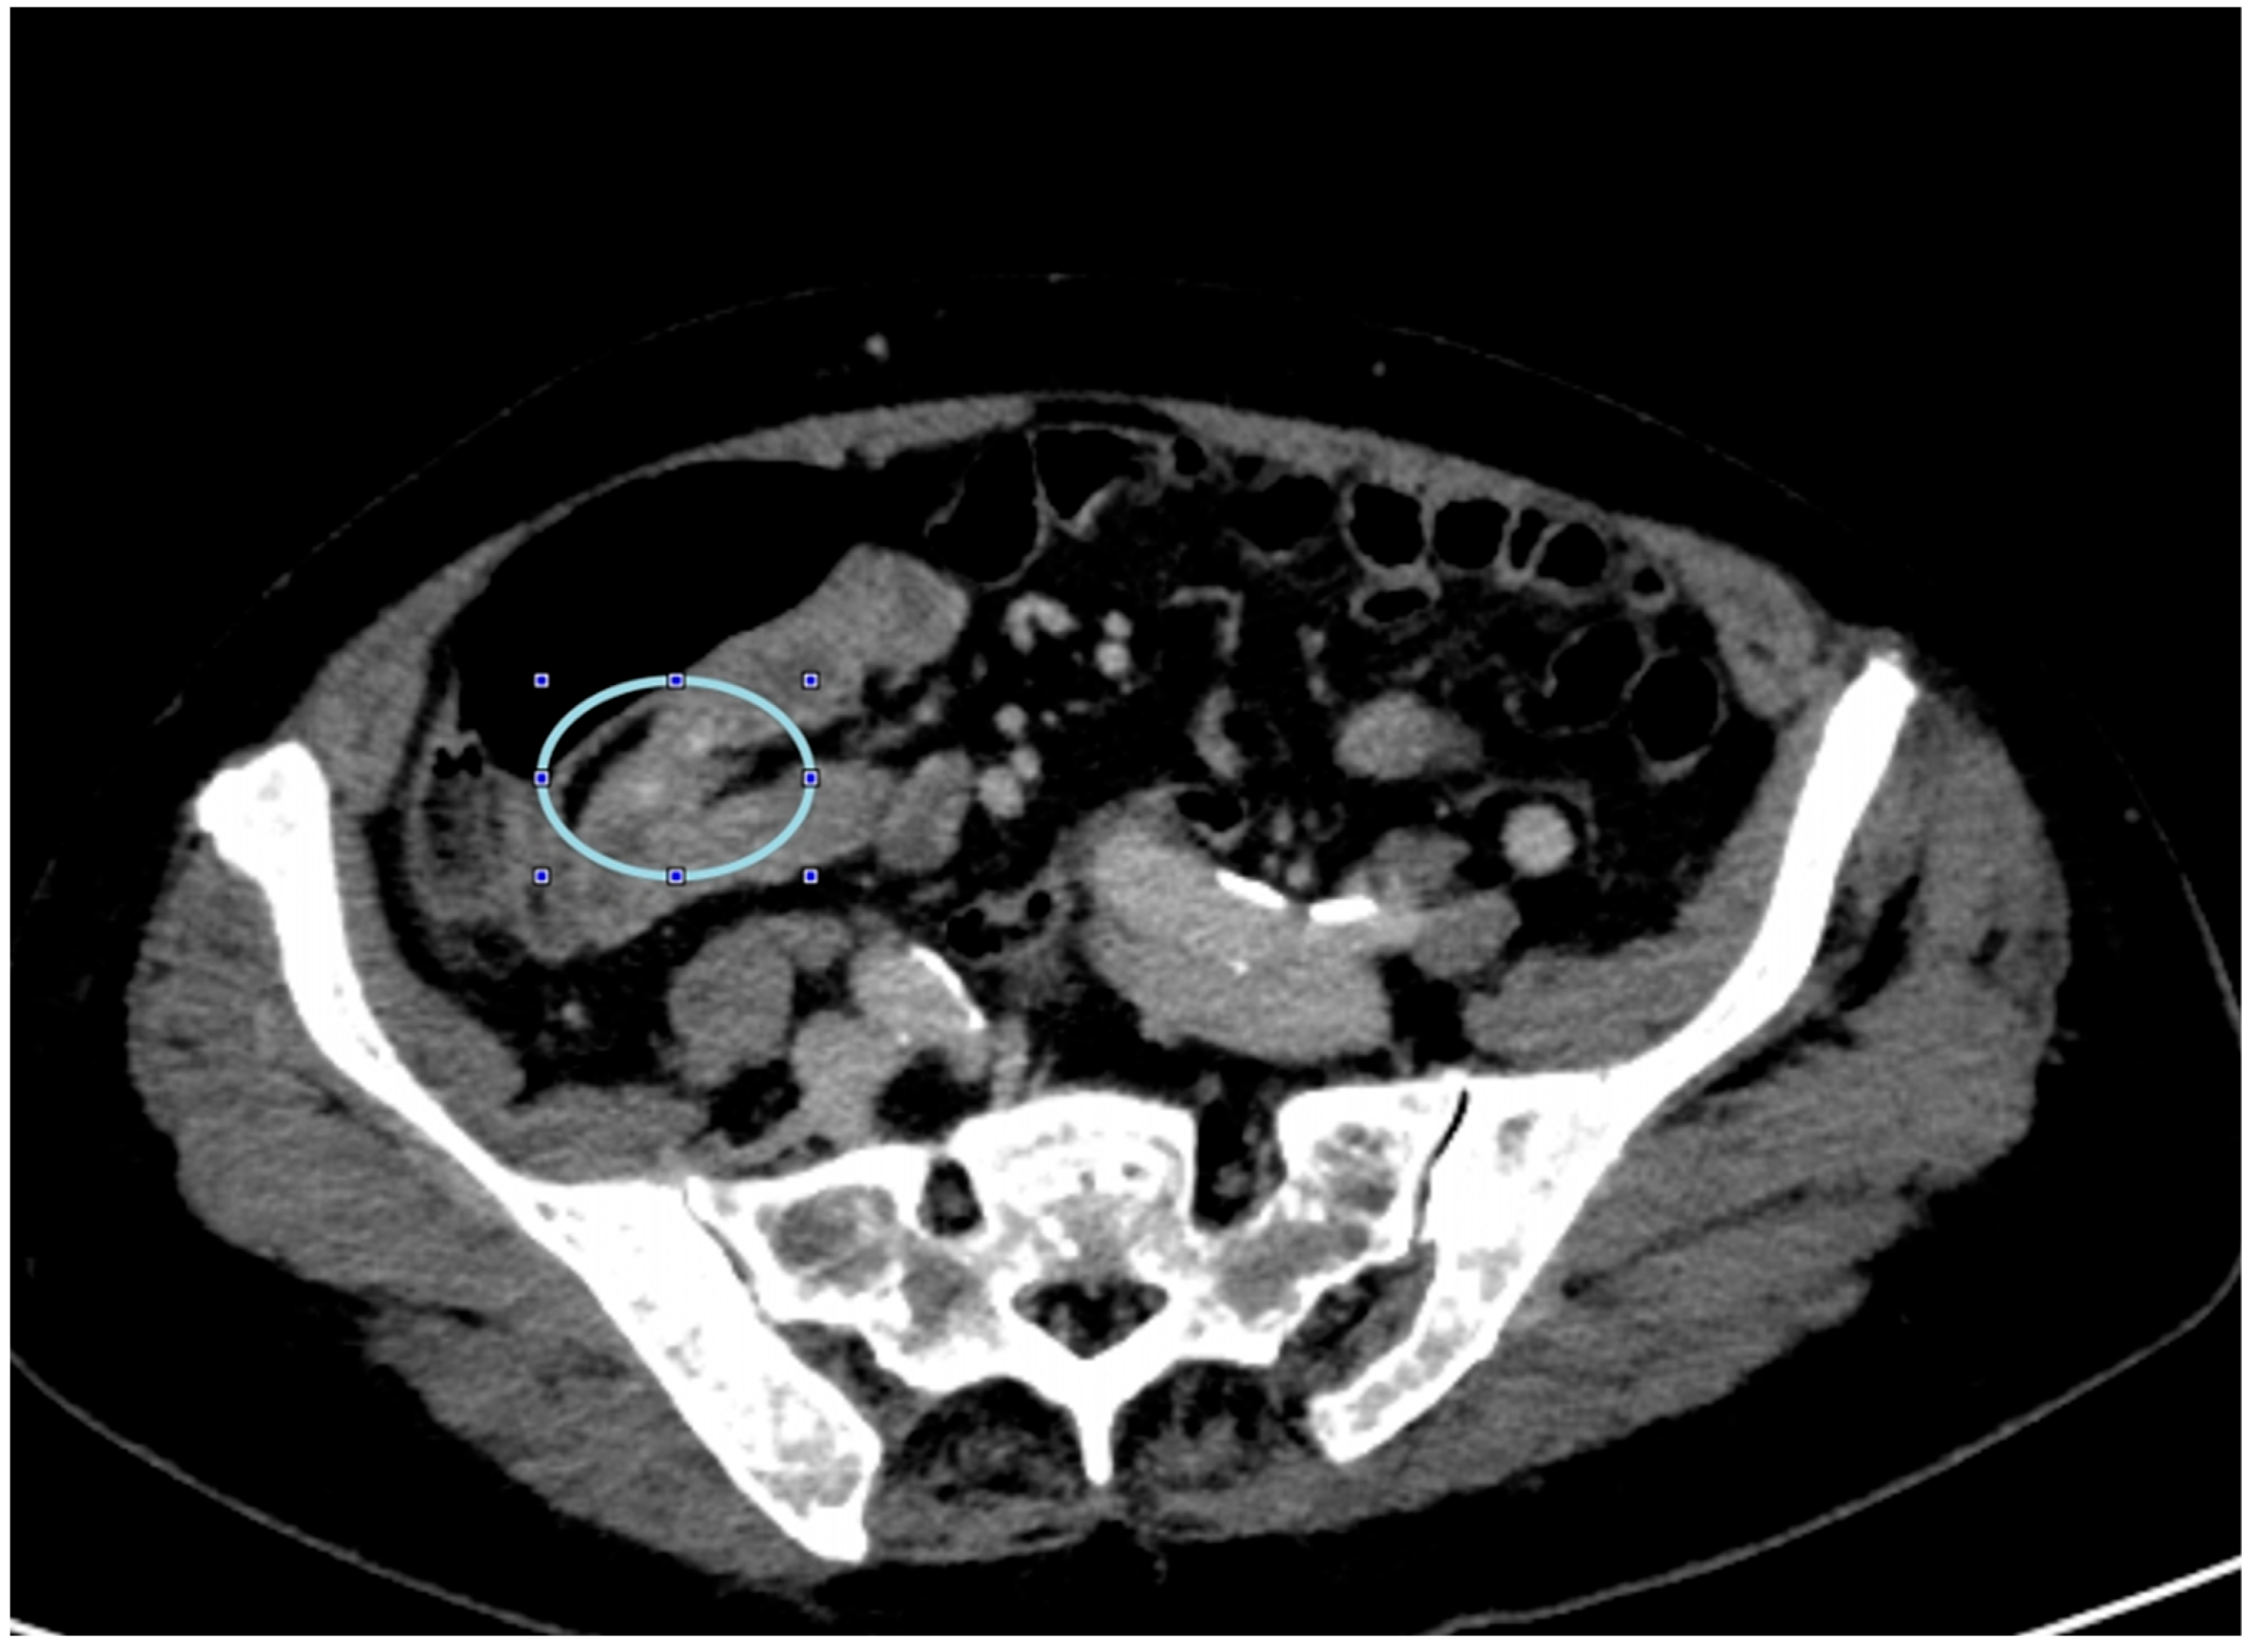

2. Case Presentation